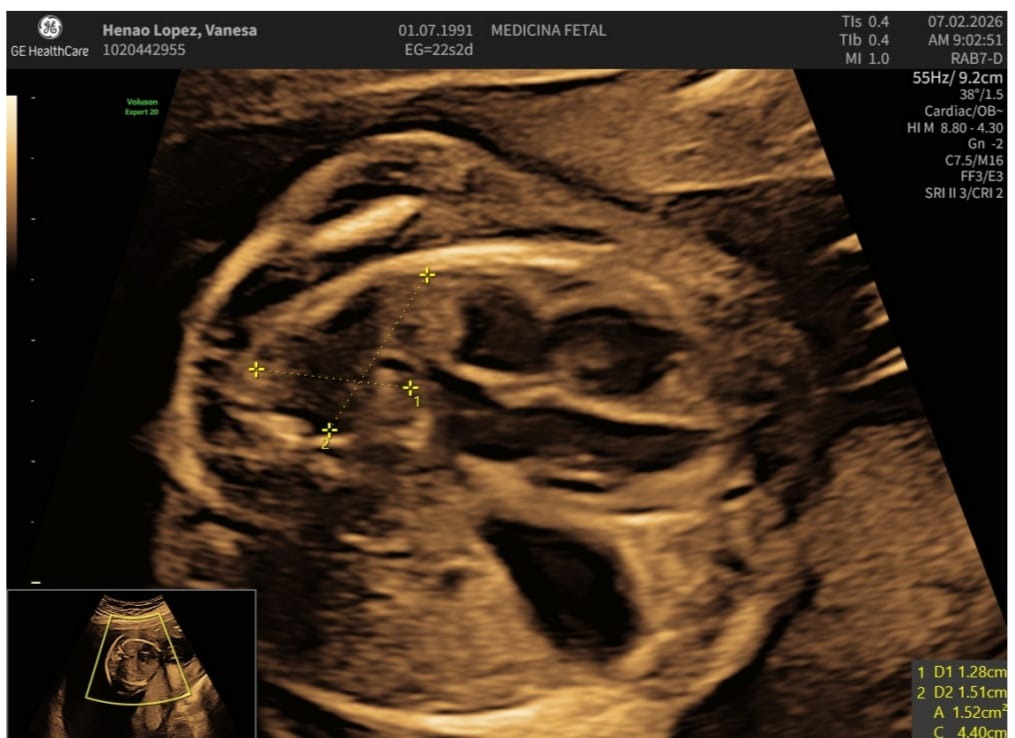

Somos Vanesa y Santiago, padres de una niña de 21 meses y actualmente esperamos con amor la llegada de nuestra segunda hija, Lucía. Sin embargo, en la semana 16 del embarazo nos informaron que nuestra hija en camino, Lucía presenta una hernia diafragmática congénita.

Esta es una condición poco frecuente que ocurre aproximadamente en 4 de cada 10.000 nacimientos. Debido a una abertura en el diafragma, algunos órganos del abdomen se desplazan hacia el tórax, impidiendo el adecuado desarrollo de los pulmones. Como consecuencia, Lucía no podrá respirar por sí sola al momento de nacer y requiere intervención intrauterina y al nacer, atención médica inmediata, cuidados intensivos y cirugía neonatal.

We are Vanesa and Santiago, parents of a 21-month-old daughter, and we are currently lovingly expecting the arrival of our second daughter, Lucía. However, at 16 weeks of pregnancy, we were informed that our unborn daughter, has a congenital diaphragmatic hernia.

This is a rare condition that occurs in approximately 4 out of every 10,000 births. It is caused by a failure in the closure of the diaphragm, because of this some abdominal organs move into the chest, preventing proper lung development. As a result, Lucía will not be able to breathe on her own at birth and will require a lot of care before, during and after delivery including intrauterine intervention and, intensive care, and neonatal surgery.